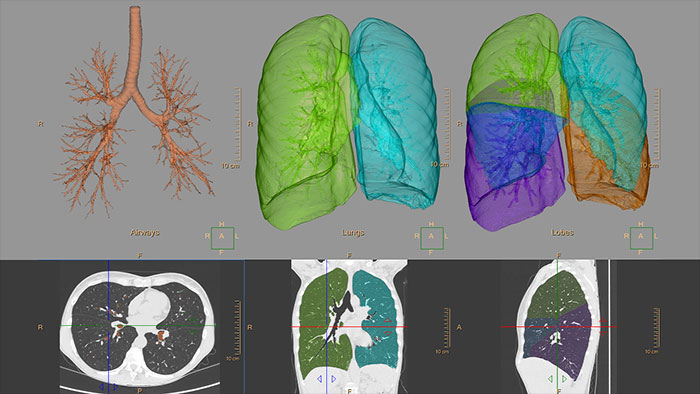

Quantify diffuse lung disease

CT COPD helps visualize and quantify the destructive process of diffuse lung disease (e.g. emphysema). The application provides a guided workflow for airway analysis, reviewing and measuring airway lumen, and assessing air trapped.